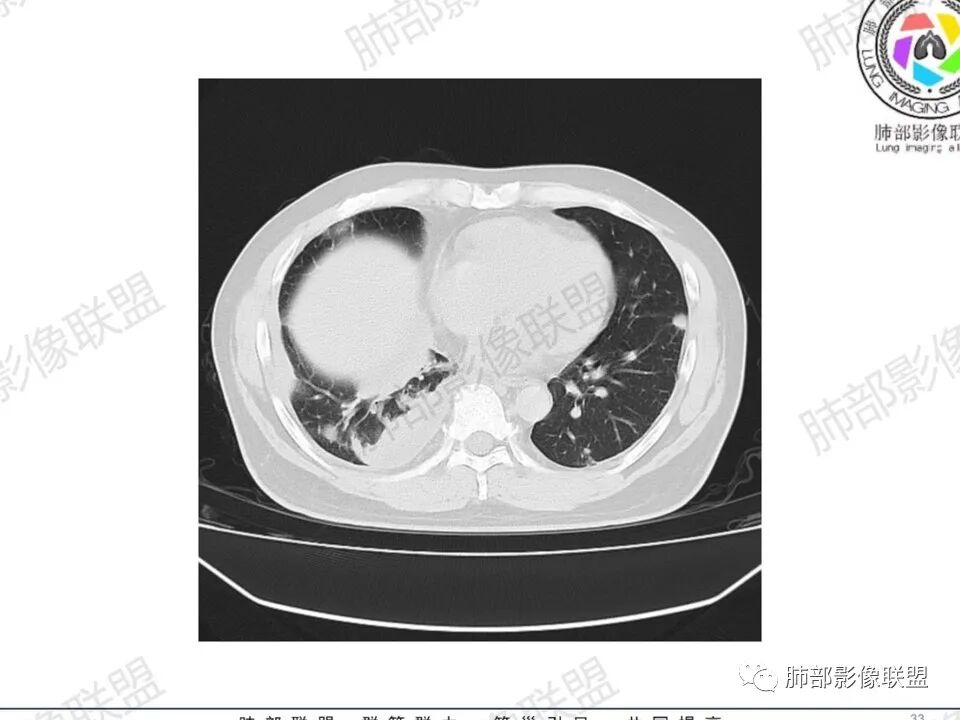

双肺多发结节,胸膜下为主,部分可见空洞。左肺上叶尖后段结节较大,分叶毛刺,周围可见长条索及小斑片影,内空洞比较光滑,内侧壁可见支气管通过。右肺下叶后基底段不张实变,后侧积液,右侧水平裂积液,右侧膈胸膜纵膈胸膜增厚积液,右侧侧胸膜肥厚,考虑1:一元金葡。2二元:金葡,左肺上叶结核。

男,45岁,左手指红肿疼痛两天,右侧胸壁疼痛伴发热12小时入院。患者急性起病,胸部CT示双肺多发结节,部分伴空洞,空洞壁较光滑,右侧胸腔积液,考虑感染性病变,金葡菌加SPE可能

中年男性,左手中指及胸壁疼痛伴发热来诊,影像见双肺多发结节,胸膜下分布为主,部分结节可见空洞,边缘模糊。左肺上叶尖后段结节较大。右肺下叶后基底段不张实变,右侧叶间裂及右侧胸腔积液,右侧侧胸膜肥厚。考虑金葡菌感染,血播SPE。

空洞内壁光滑,偏心厚壁空洞,张力高

胸水,部分包裹